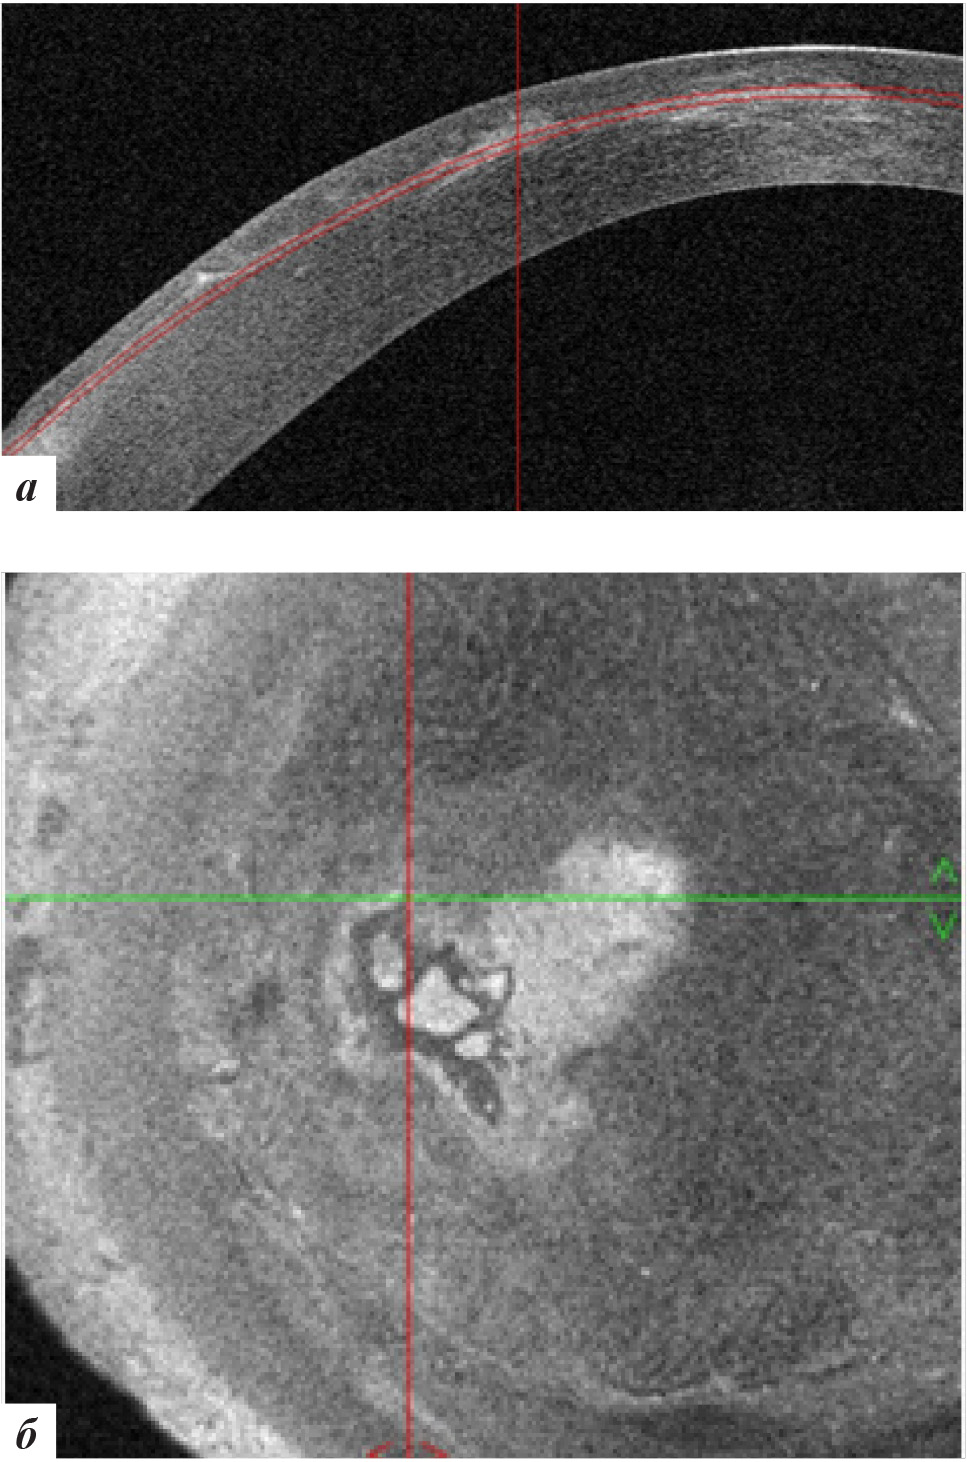

Рис. 2. Данные ОКТ роговицы правого глаза: а – горизонтальная проекция; б – фронтальная проекция

Рис. 4. Данные ОКТ роговицы левого глаза: а – горизонтальная проекция, б – фронтальная проекция